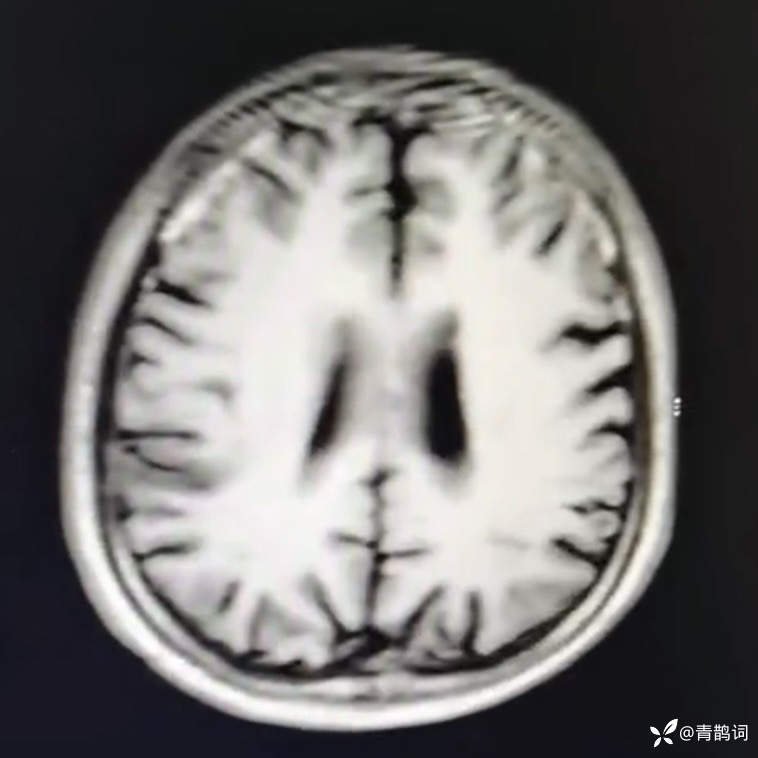

乐痴于医等 2人推荐简要病史:42岁男性,记忆力下降及听力下降一年余。既往体健,否认前驱感染病史。否认家族史。三个月前就诊于当地医院,自述腰穿脑脊液乳酸增高。现就诊于我院,查体记忆力下降,计算力下降,定时定向差,吟诗样语言。完善磁共振如下:

FLAIR: